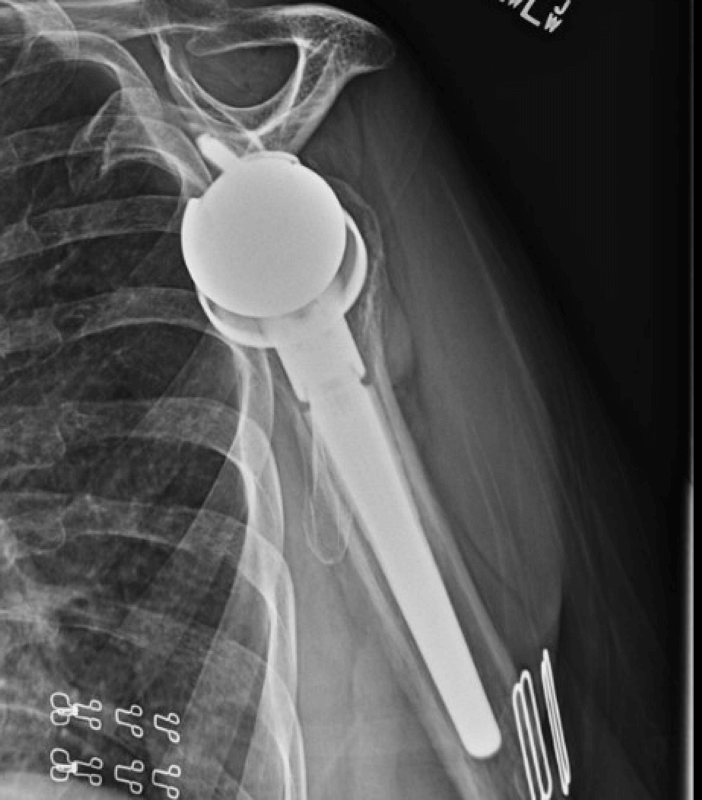

OTHER IMAGES